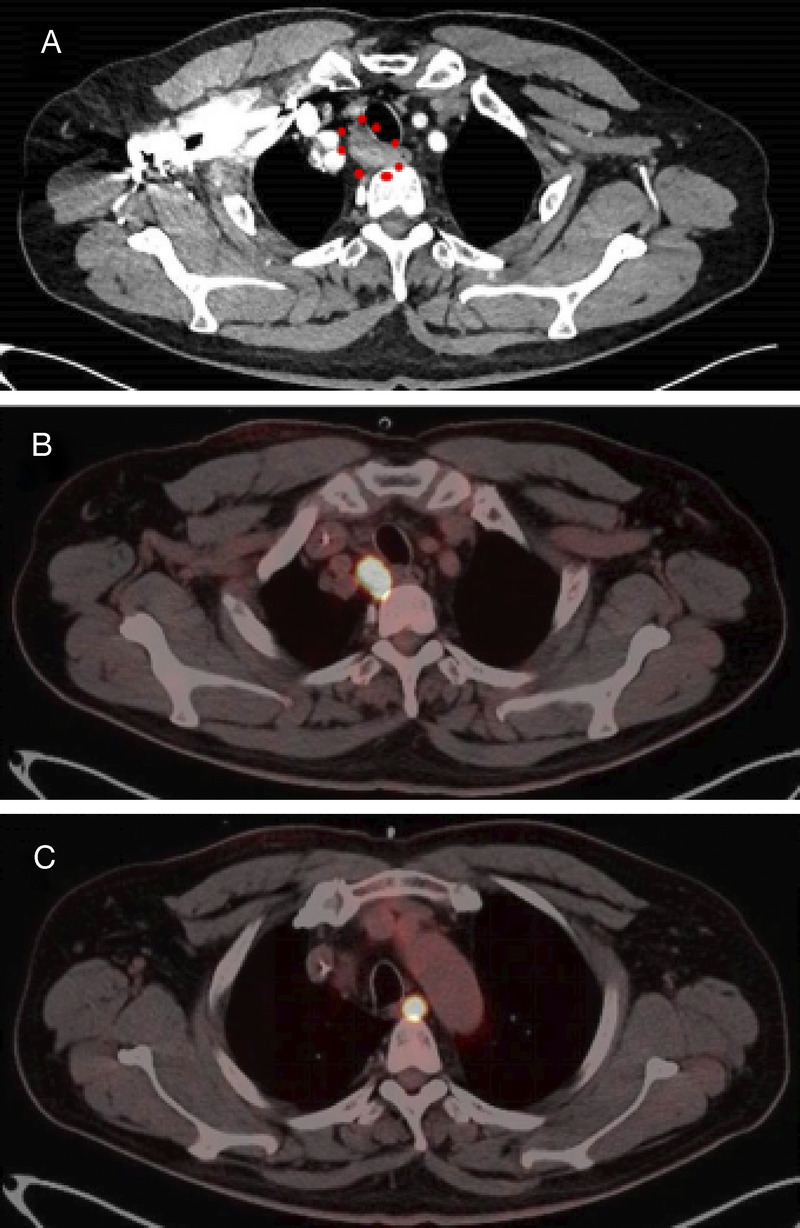

Occult synchronous multiple primary esophageal squamous cell carcinoma with mediastinal metastasis (with video).